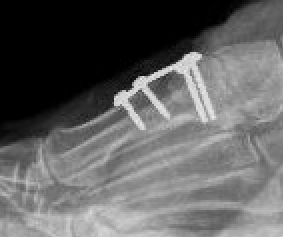

Jones procedure

- IPJ fusion

- EHL tendon transfer